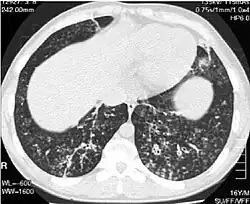

High-resolution computed tomography images of the lower chest in a 16-year-old boy with diffuse panbronchiolitis

Diagnosis

High resolution computed tomography (HRCT) images of the lower chest in a 16-year-old boy initially diagnosed with DPB (left), and 8 weeks later (right) after a 6-week course of treatment with erythromycin. The bilateral bronchiectasis and prominent centri-lobular nodules with a "tree-in-bud" pattern shows noticeable improvement.

The diagnosis of DPB requires analysis of the lungs and bronchiolar tissues, which can require a lung biopsy, or the more preferred high resolution computed tomography (HRCT) scan of the lungs.[7] The diagnostic criteria include severe inflammation in all layers of the respiratory bronchioles and lung tissue lesions that appear as nodules within the terminal and respiratory bronchioles in both lungs.[4] The nodules in DPB appear as opaque lumps when viewed on X-rays of the lung, and can cause airway obstruction, which is evaluated by a pulmonary function test, or PFT.[6] Lung X-rays can also reveal dilation of the bronchiolar passages, another sign of DPB. HRCT scans often show blockages of some bronchiolar passages with mucus, which is referred to as the "tree-in-bud" pattern.[7] Hypoxemia, another sign of breathing difficulty, is revealed by measuring the oxygen and carbon dioxide content of the blood, using a blood test called arterial blood gas. Other findings observed with DPB include the proliferation of lymphocytes (white blood cells that fight infection), neutrophils, and foamy histiocytes (tissue macrophages) in the lung lining. Bacteria such as H. influenzae and P. aeruginosa are also detectable, with the latter becoming more prominent as the disease progresses.[4][5] The white blood, bacterial and other cellular content of the blood can be measured by taking a complete blood count (CBC). Elevated levels of IgG and IgA (classes of immunoglobulins) may be seen, as well as the presence of rheumatoid factor (an indicator of autoimmunity). Hemagglutination, a clumping of red blood cells in response to the presence of antibodies in the blood, may also occur. Neutrophils, beta-defensins, leukotrienes, and chemokines can also be detected in bronchoalveolar lavage fluid injected then removed from the bronchiolar airways of individuals with DPB, for evaluation.[4][9]